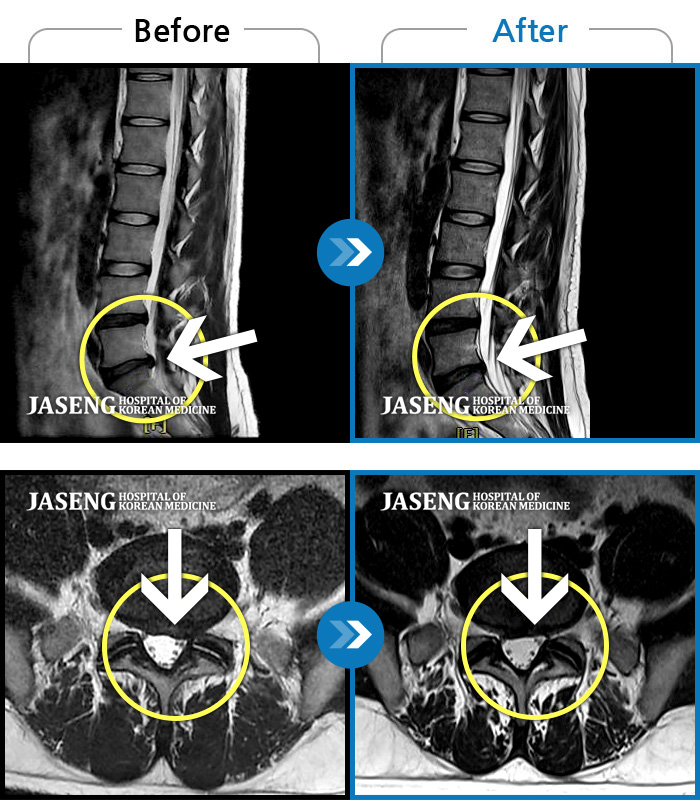

허리디스크

광주 · 장영우 원장

양측 허리부터 골반 묵직한 통증, 좌측 다리 외측까지 이어지는 당기는 통증으로 내원하셨습니다.

촬영시기

2503.04.01 ~ 2509.11.01

2025.09.22